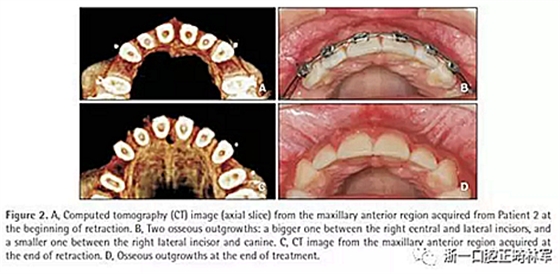

16歲,女性,主訴為上牙前突。骨性II類,安氏II類1分類。治療方案需要拔除上頜第一前磨牙。

在內(nèi)收的第二個月出現(xiàn)了兩個單獨的骨性凸起:在有中切牙和側(cè)切牙間有一個大的凸起,在右側(cè)切牙和尖牙間有一個小的凸起(圖2)。直到治療結(jié)束凸起都沒有消退(圖3)。內(nèi)收耗時11個月。